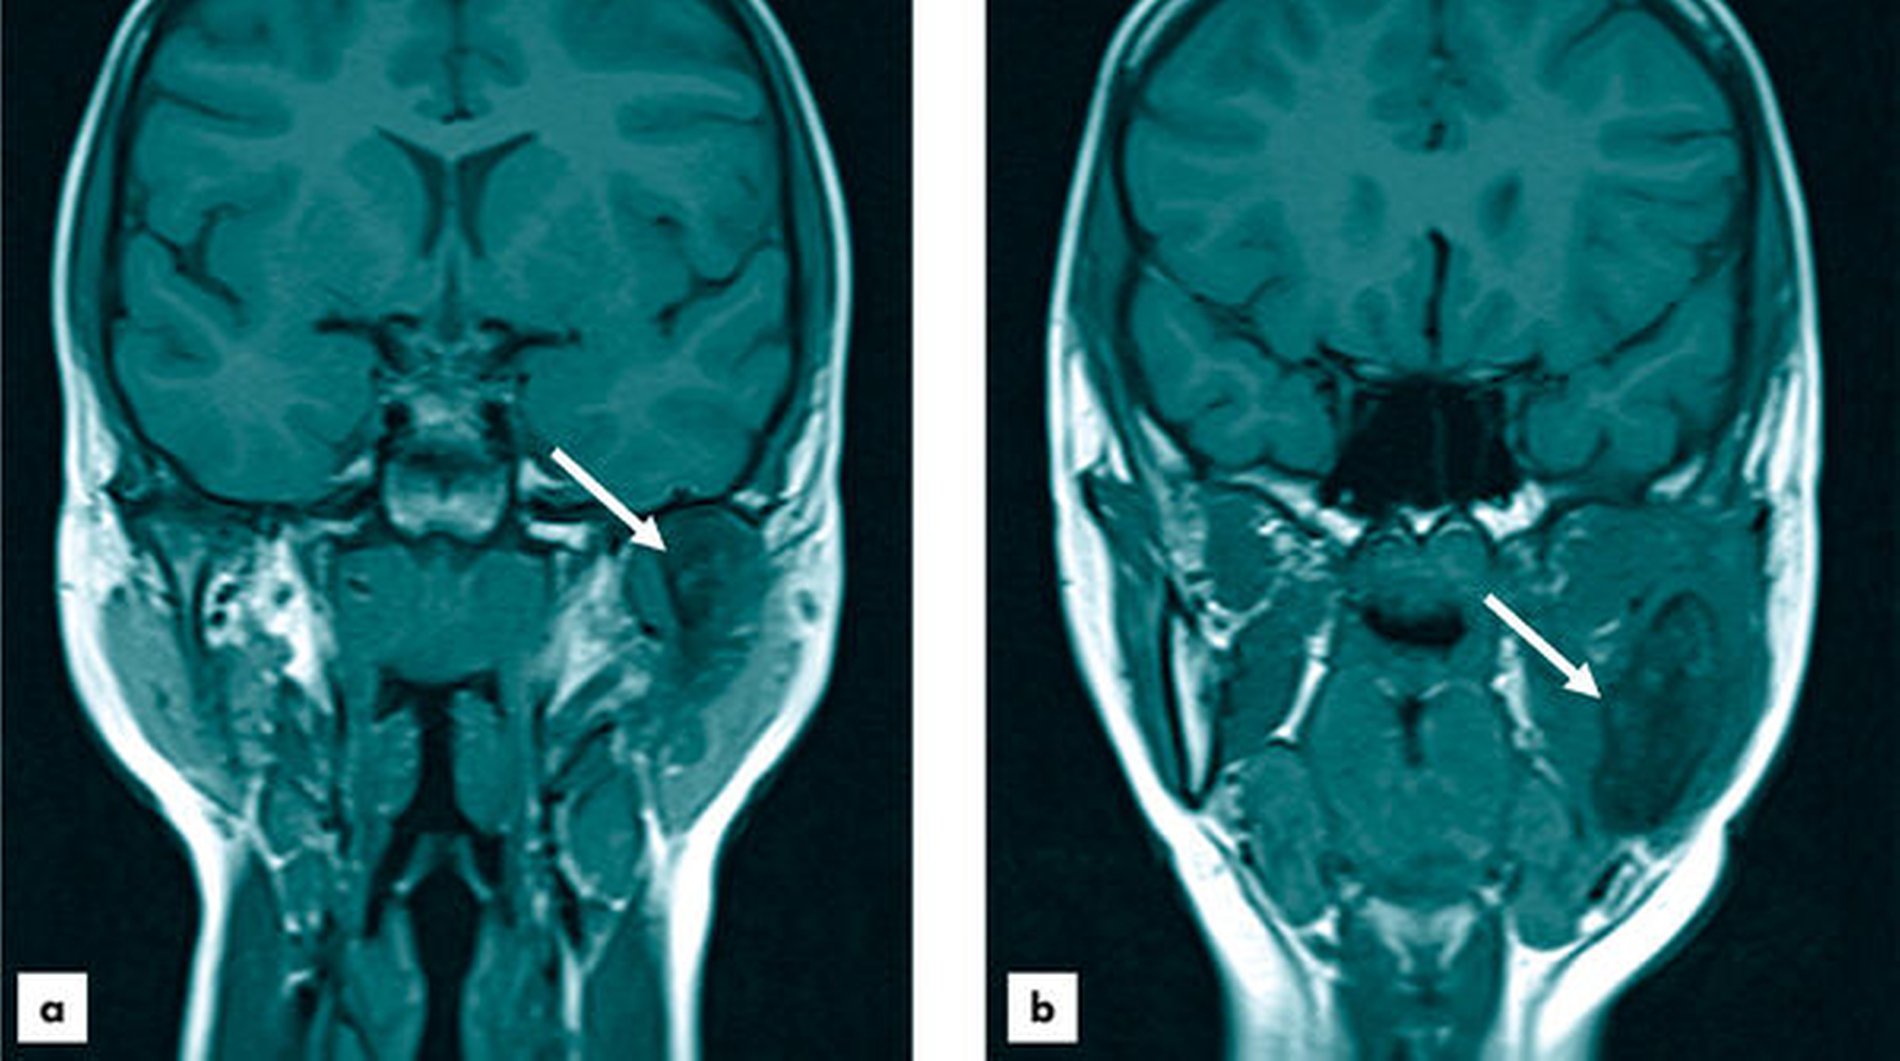

Aktuell befindet sich die heute zwölfjährige Patientin im regelmäßigen Recall in ambulanter Sprechstunde. Aktuelle radiologische Verlaufskontrollen zeigen eine minimale Progredienz der dysplastisch veränderten Knochenanteile des linken Unterkiefers (MRT, Abbildung 4). Unter bedarfsgerechter Analgesie mit Paracetamol und Novaminsulfon bei episodischen Schmerzen sind im Kontext der geringfügigen Progredienz, aber sonstigen Beschwerdefreiheit weitere, kurzfristige Verlaufskontrollen mittels MRT vereinbart.